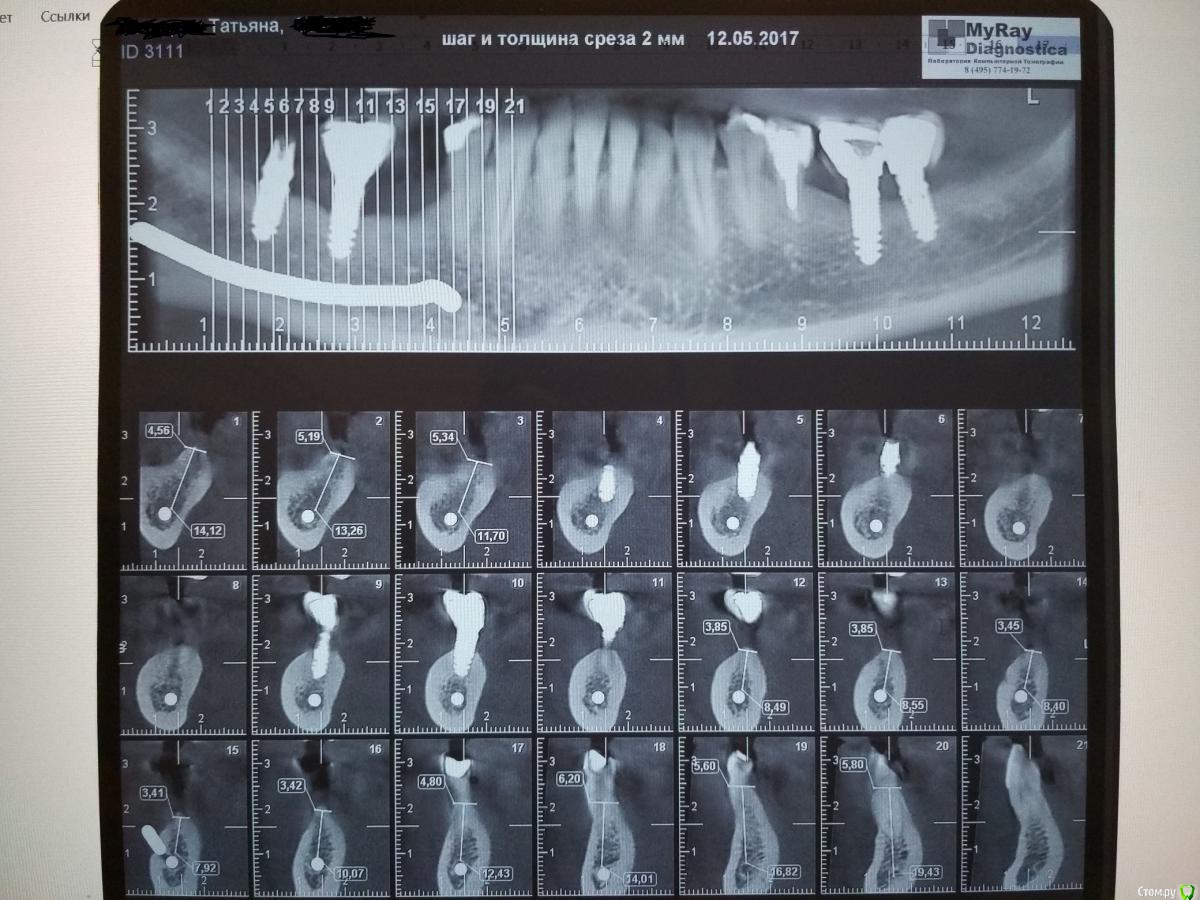

Татьяна_2010 Опубликовано 4 ноября, 2019 Поделиться Опубликовано 4 ноября, 2019 Уважаемые врачи!Посоветуйте, пожалуйста, что лучше предпринять в области 5 зуба справа внизу. История следующая. В 2011 году поставили за раз 7 имплантов. Три сверху слева (через пол года после синус лифтинга) и по 2 импланта внизу (шестерка и семерка) слева и справа. Так как жевать было нечем, то поставили протез, который крепился за пятые зубы. Через месяц пятерки расшатались. Справа 5-ку пришлось удалить. В 2013 году в районе 5-ки справа было проведено две операции по имплантации. Дважды имплант не прижился. При исследовании микрофлоры верхних дыхательных путей и зева был обнаружен золотистый стафилококк. В 2017 году справа с 7-ки слетела коронка с импланта. Обратно ее не поставили, так как десна просела и предложили консоль. Коронки на 7 и 6 зубе будут держать коронку над 5-м. Я бы очень не хотела использовать этот вариант. До нерва под 5-кой было 8 мм в 2017 году, сейчас возможно меньше. Десна совершенно тонкая (узкий альвеолярный гребень). Можно ли в моем случае нарастить десну и при хороших анализах поставить имплант? Заранее спасибо! Ссылка на комментарий

Татьяна_2010 Опубликовано 6 ноября, 2019 Автор Поделиться Опубликовано 6 ноября, 2019 Спасибо Вам Irouil и Антон ТЛТ!Мне больше нравится 2 вариант. После того как уехала мой врач имплантолог, которой я доверяла полностью, обошла много клиник, в том числе институт стоматологии в Москве, и везде мне говорили, что костная пластика не для меня. Одно пояснение я запомнила- так как у меня отсутствует губчатая кость с кровеносными сосудами в области 5-ки и соответственно, подсаживаемый костный материал будет очень долго прорастать сосудами (если вообще будет), медленнее будет идти образование кости. Вы рассматриваете вариант костной пластики! Я очень рада! А у меня действительно нет этой губчатой кости? Методики костной пластики почитала, но так и не поняла, если действительно нет этой губчатой кости, то каким образом будет «прирастать» подсаживаемый материал? Почитала ваш форум. Вдохновляют работы врачей, пришло понимание, что и в области стоматологии медицина продвинулась вперед. Под впечатлением от работ Карена Габриеляна, врача от Бога. Уходят лучшие, вечная ему память. Я верю, что есть и другие врачи делающие невозможное возможным. Ссылка на комментарий